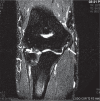

Medial elbow pain

Medial elbow pain is uncommon when compared with lateral elbow pain.Medial epicondylitis is an uncommon diagnosis and can be confused with other sources of pain.Overhead throwers and workers lifting heavy objects are at increased risk of medial elbow pain.Differential diagnosis includes ulnar nerve disorders, cervical radiculopathy, injured ulnar collateral ligament, altered distal triceps anatomy or joint disorders.Children with medial elbow pain have to be assessed for 'Little League elbow' and fractures of the medial epicondyle following a traumatic event.This paper is primarily focused on the differential diagnosis of medial elbow pain with basic recommendations on treatment strategies. Cite this article: EFORT Open Rev 2017;2:362-371. DOI: 10.1302/2058-5241.2.160006.